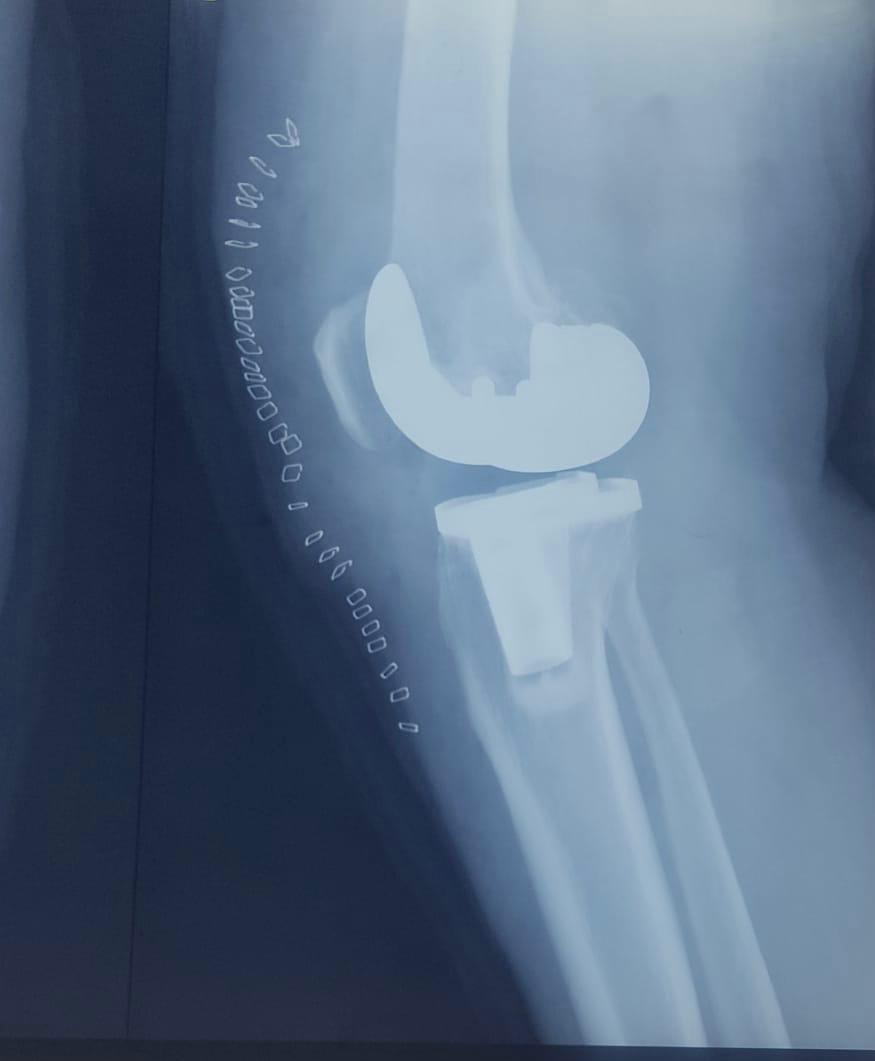

Joint replacement surgery is offered for patients suffering from severe joint pain, stiffness, and reduced mobility due to degenerative joint conditions. The goal of joint replacement is to relieve pain, restore movement, and improve overall quality of life through modern surgical techniques and structured post-operative care.

Total knee and total hip replacement surgeries are performed for advanced joint damage where conservative treatment is no longer effective. These procedures help restore joint function, reduce chronic pain, and allow patients to return to daily activities with improved mobility and comfort.